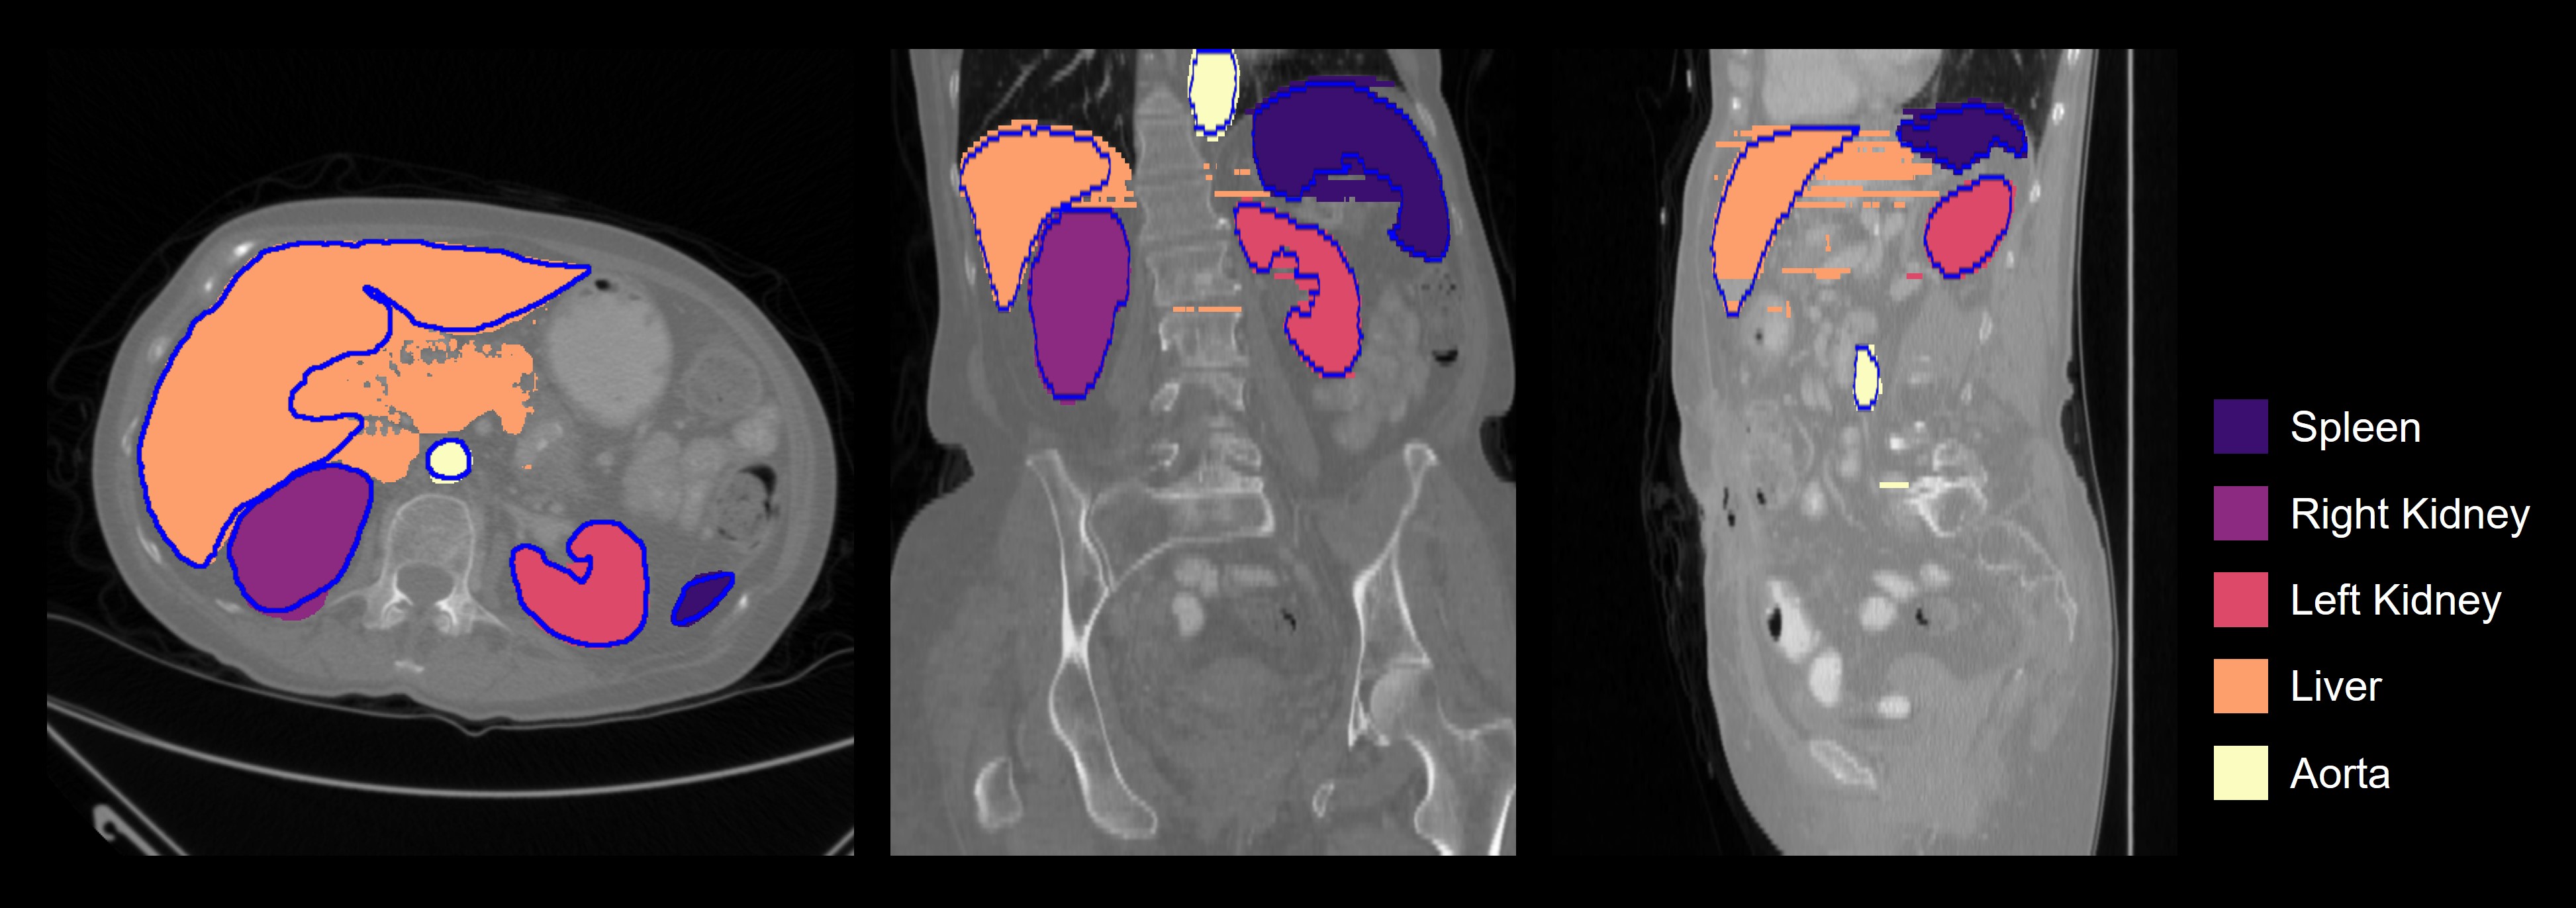

Refer to caption

Figure 4: An example of crowd-sourced SAM-generated annotations for a CT scan from the BTCV training set in the axial, coronal, and sagittal views. The SAM-generated annotations are filled in while the ground-truth annotations are outlined in blue.

The non-expert annotators annotated 651 slices from n=15𝑛15n=15 volumes in the BTCV training set with 1840 bounding boxes using our data curation pipeline (Figure 4). They took 55.60±8.76plus-or-minus55.608.7655.60\pm 8.76 mins to annotate an organ of interest across all volumes, with a mean of 3.29±1.04plus-or-minus3.291.043.29\pm 1.04 seconds per slice. Out of n=15𝑛15n=15 volumes, the non-experts annotated all five organs of interest for n=11𝑛11n=11 volumes (73%). For the remaining n=4𝑛4n=4 volumes (27%), annotations for left and right kidneys were missing for n=3𝑛3n=3 volumes (75%), liver was missing for n=2𝑛2n=2 volumes (50%), and spleen was missing for n=1𝑛1n=1 volume (25%).

Figure 5: An example of (a) GT-nnU-Net and (b) SAM-nnU-Net segmentations for a CT scan from the BTCV test set in the axial, coronal, and sagittal views. The models are trained on fully annotated n=11 volumes from the BTCV training set. The predicted segmentations are filled in while the ground-truth annotations are outlined in blue.

However, our results indicate that while SAM-generated annotations exhibit high mean slice Dice scores compared to ground-truth annotations, the SAM-nnU-Net models perform significantly worse than the GT-nnU-Net models across the simulated setting and the crowd-sourced setting for the segmentation of abdominal organs using CT scans (p<0.001𝑝0.001p<0.001, all). This discrepancy is due SAM being primarily designed for 2D semantic segmentation, thereby resulting in a lack of spacial relationships between features in 3D (e.g., depth) and poor ”connectivity” in annotations between two consecutive slices (Figure 4). As indicated by our results, this leads to significantly worse mean volume Dice scores for SAM-generated annotations when compared to ground-truth annotations and translates into sub-optimal performance for the SAM-nnU-Net models, despite nnU-Net being a SOTA model architecture.